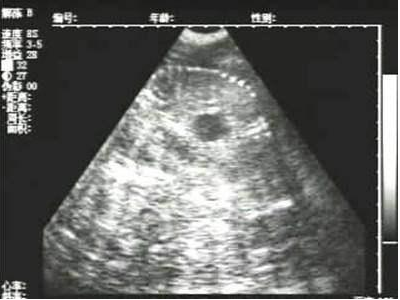

懷孕后期胎兒骨骼圖像

需要注意的是,出現(xiàn)云團(tuán)狀必須雙側(cè)檢查加以確認(rèn).根據(jù)B超機(jī)顯示圖我們大致可以判斷孕齡.圖像呈橢圓或者卵圓形大致為30天左右孕齡;圖像呈橢圓形或者卵圓形外,有明顯發(fā)亮骨骼圖像大致為50孕齡左右;圖像囊胚消失,發(fā)亮處隱約可見(jiàn)竹節(jié)狀東西為成型胎兒骨骼,一般為后期80孕齡以后。一般B超機(jī)成像會(huì)出現(xiàn)三種顏色,白色、黑色、灰色。白色為密度較高的物體,如骨骼或者結(jié)實(shí).黑色一般為液體,包括血液、羊水、組織間隙液體、炎癥病灶等?;疑话銥閷?shí)質(zhì)性物質(zhì),如肌肉。